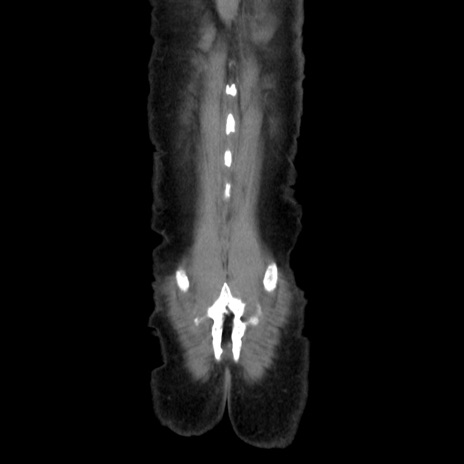

症例37(冠状断像)

【症例】40歳代 男性

【主訴】腹痛

【現病歴】4時間ほど前に電車に乗車中に臍部上より腹痛出現。徐々に増悪し起立困難となり、救急外来受診。生ものは数日食べていない。今朝お雑煮を食べた。

【身体所見】BT 36.8℃、BP 117/84mmHg、HR 91/min、SpO2 97%、苦悶様、腹部:臍上部広範囲圧痛あり、反跳痛±

【データ】WBC 8100、CRP 0.03